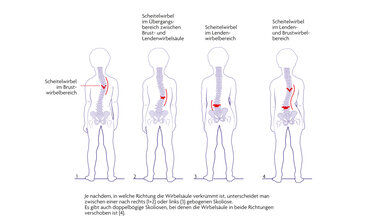

3. Nach dem betroffenen Abschnitt der Wirbelsäule

- Brustwirbelsäule (thorakal)

- Lendenwirbelsäule (lumbal)

- Übergang zwischen Brust- und Lendenwirbelsäule (thorakolumbal)

- Brust- und Lendenwirbelsäule (thorakale und lumbale Skoliose)

© W&B/Dr. Ulrike Möhle

- C-förmig

- S-förmig

- Doppel-S-förmig (triplebogige-Skoliose)